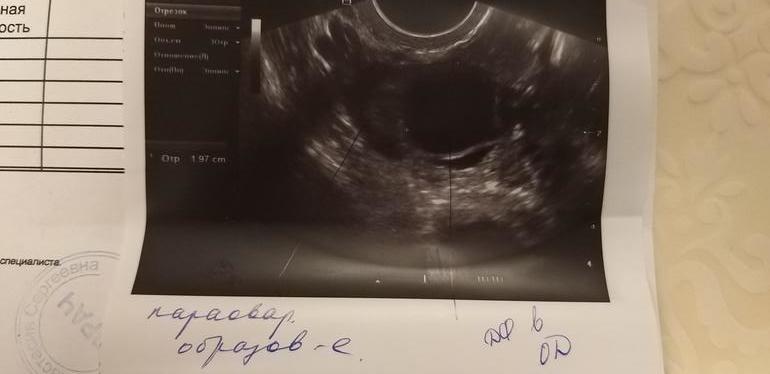

3. В правом Я ДФ 19-20 мм, но труба правая расширена 5*20 мм😰 Как такое возможно?😱 Ведь я считала именно эту трубу 100 % здоровой, и Б 5 мес назад была с этой трубы, так как ЖТ было справа. После чистки было уже куча Узи и ни о каком расширении трубы речи не шло.